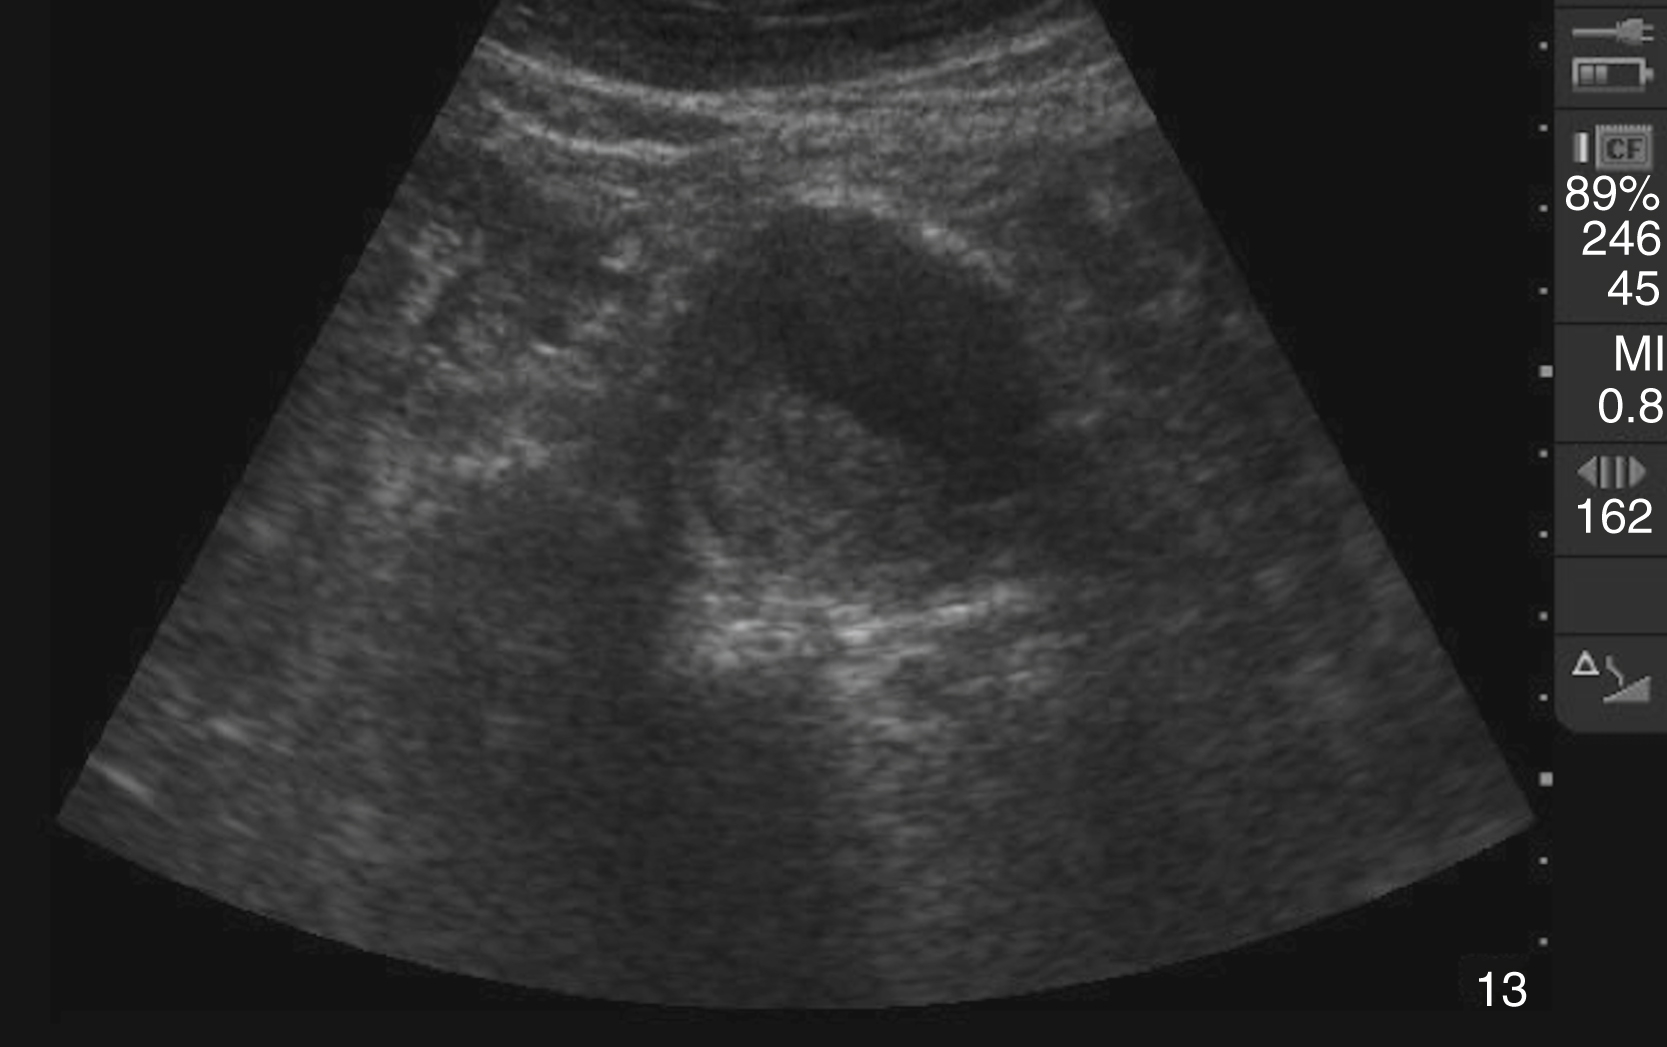

Pathology

Hydronephrosis is characterized by dilation and anechoic fluid accumulation within the renal pelvis and calyces, ranging from mild to severe ( Fig. e3.6 ). Renal and/or ureteral calculi may be identified as echogenic foci with associated shadowing and are usually located within the kidney (nonobstructive) or in the renal pelvis, proximal ureter, or uretero-vesicular junction. Color Doppler placed over the kidney can help differentiate mild hydronephrosis from the renal vasculature, as well as possibly accentuate any renal stones by producing the renal twinkle artifact.

Hydronephrosis with dilation of the calyces and renal pelvis of the kidney showing thinning of the cortex, signifying severe hydronephrosis.